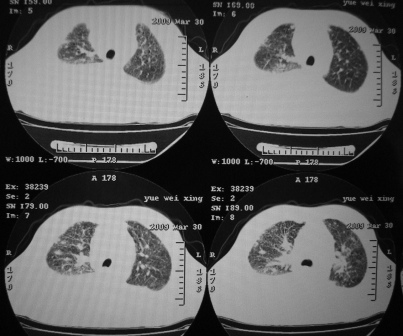

xx 男 43岁

右下叶支气管变窄闭塞,右下叶实变,双肺野弥漫性斑片状影,肺纹理增多增粗,纵隔多发淋巴结肿大,双侧胸水,考虑1双肺继发型结核,右下叶支气管内膜结核,双侧胸水2右下叶中央型肺癌伴右下叶实变,双肺转移,纵隔淋巴转移,双侧胸腔积液3淋巴瘤,请结合病史进一步检查。

右肺下叶支气管中断闭塞,右下肺见不规块影,并胸腔积液,考虑肺中央型肺癌继发下叶不张,\\双侧胸腔积液,心包积液。

考虑右中央型肺癌并下叶不张,双侧胸腔积液,心包积液

右侧中央型肺癌伴右肺下叶不张,双肺及纵隔淋巴转移,双侧胸腔积液,心包积液。

1)考虑右侧中央型肺癌伴右肺下叶不张,双肺及纵隔淋巴转移。2)双侧胸腔积液,以右侧为甚。3)心包积液。